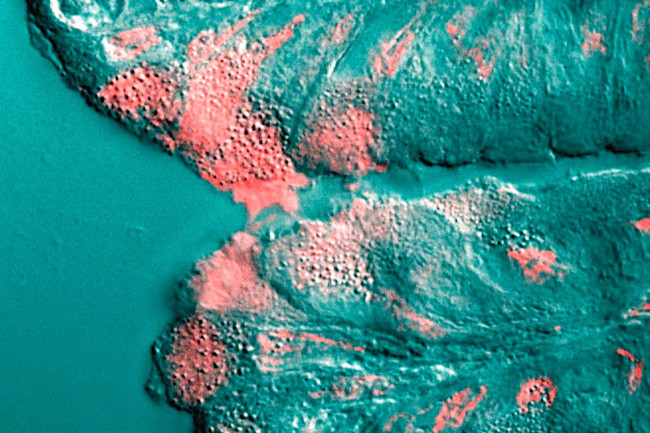

Mucus (shown in pink) is secreted by a cell in the stomach. (Credit: Underwood 2006 PLoS Biology)